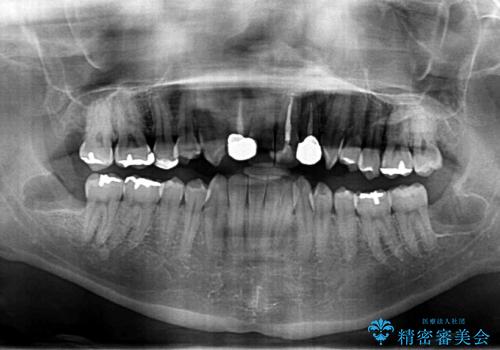

- 親知らず抜歯をしたいが、恐怖心が強く、静脈内鎮静(リラックス麻酔)下での施術を希望され来院されました。

静脈内鎮静法は、ほとんど記憶のないうちに手術を終えることを可能にする麻酔法になります。